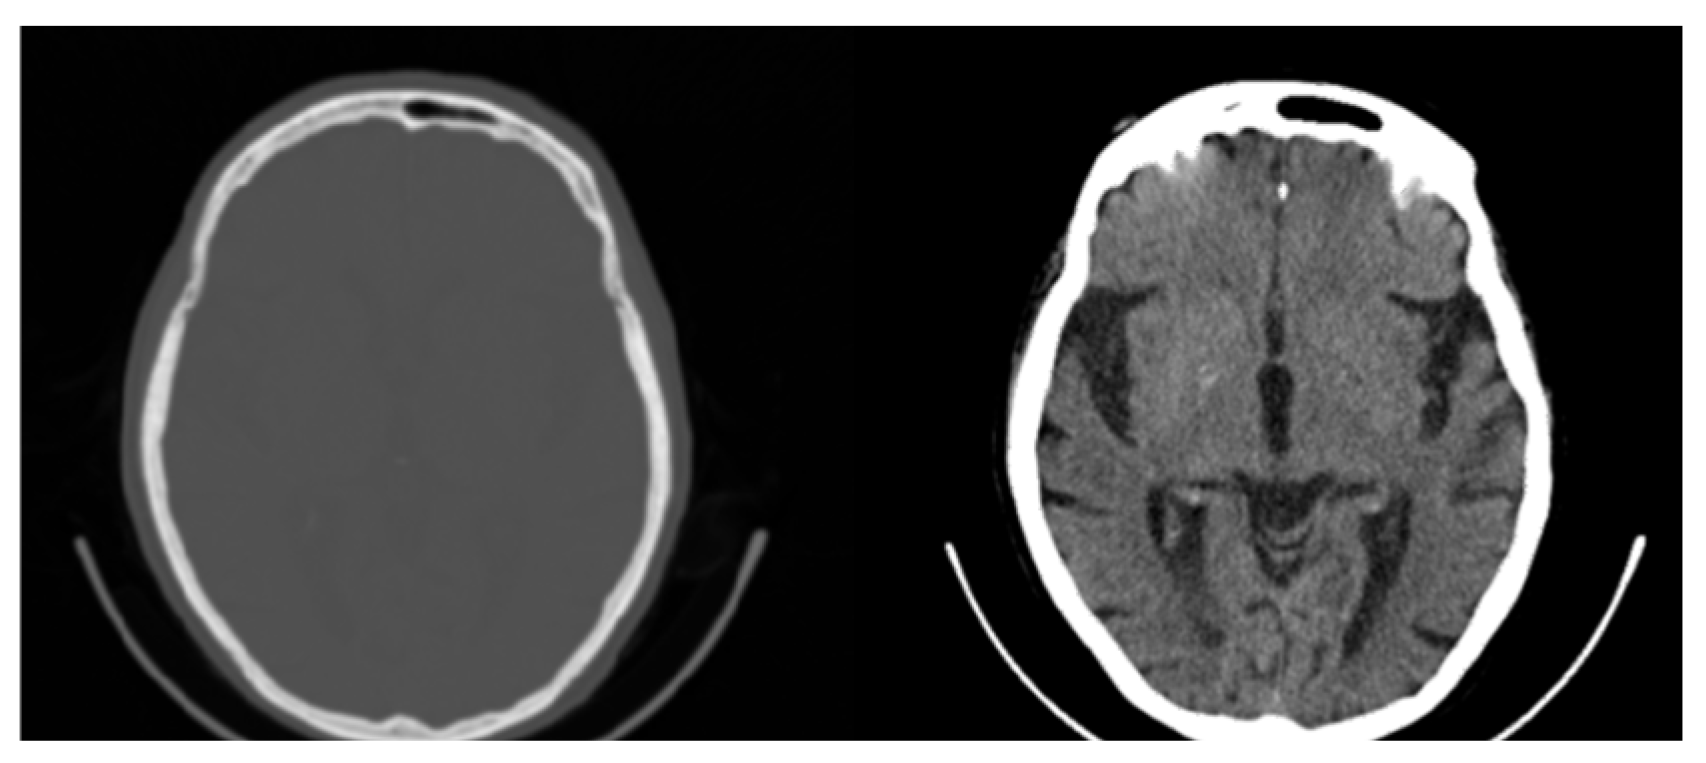

Figure 2.

Original CT slice in grayscale (left) followed by Red, Green, and Blue coloring. Gray and Green shades outperform Red and Blue in terms of the discernibility of the structures.